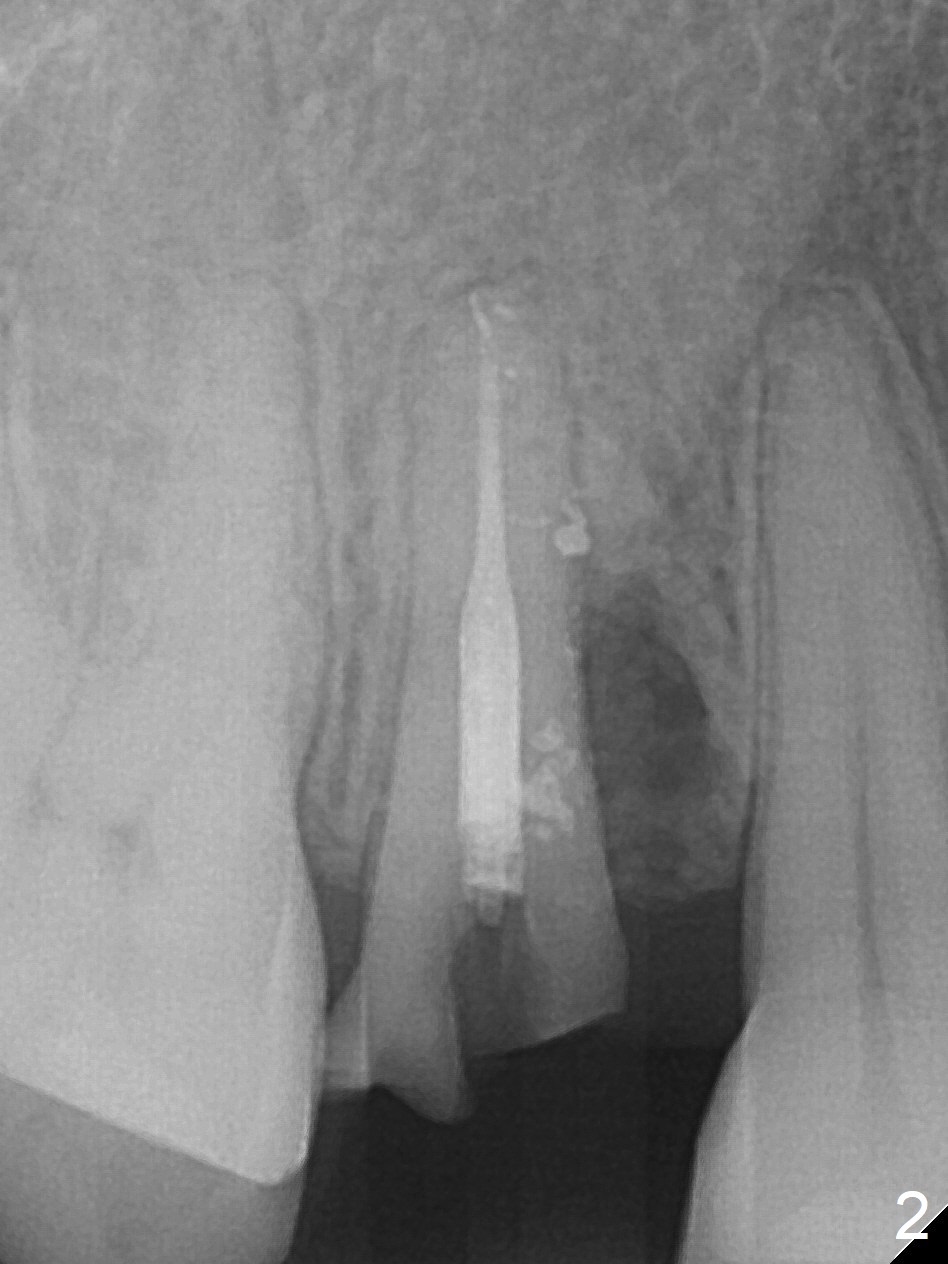

Seven years post RCT (Fig.1), the tooth #4 of a 65-year-old woman fractures subgingival palatally (Fig.2). Since the root of the affected tooth is close to the tooth #3, osteotomy is established in the mesial slope of the socket (Fig.3). Change the trajectory once the drill has penetrated the lamina dura of the socket (Fig.4). The initial depth will be 20 mm for a 3.8x16 mm implant (Fig.5).